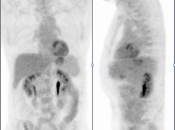

- Maximum Intensity Projection (MIP)

- 3-D Rotating MIP & Coronal “Quick MIP”

- Coronal PET

- Sagittal PET